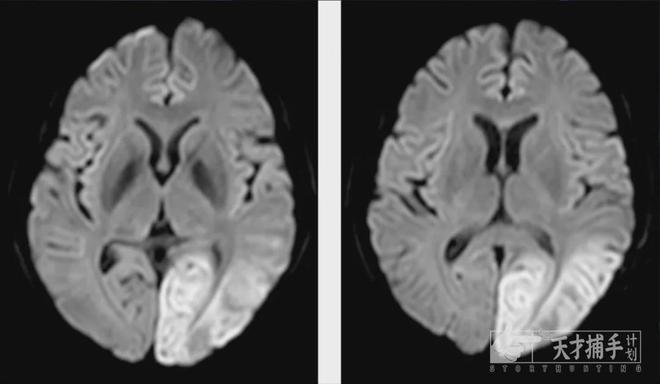

¡¡¡¡ËäÈ»X¹âµÈÓ°Ïñѧ¼ì²éÊÇÕï¶ÏÏ¥¹Ç¹Ø½ÚÑ×µÄÖØÒª¹¤¾ß±ØÍþ£¬µ«²»Í¬½×¶ÎµÄ²¡±ä±íÏÖ¿ÉÄܲ»Í¬£¬ÇÒÊܵ½É豸ÐÔÄܺÍÒ½Éú¾­ÑéµÄÓ°Ï죬¿ÉÄܵ¼ÖÂÕï¶ÏÆ«²î¡£

¡¡¡¡½¨ÒéÒ½ÉúÓ¦½áºÏ»¼ÕߵIJ¡Ê·¡¢Ö¢×´¡¢ÌåÕ÷¼°Ó°Ïñѧ¼ì²é½á¹û½øÐÐ×ÛºÏÅжÏ£¬±ØÒªÊ±ÑûÇë¶àѧ¿Æ×¨¼Ò»áÕÒÔÌá¸ßÕï¶ÏµÄ׼ȷÐÔ¡£